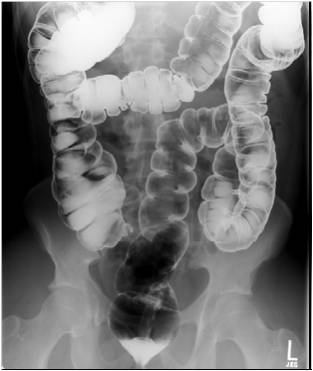

Image

Fig.20.: Follow-through examination

On the abdominal radiograph distension of the small bowel loops and air-fluid levels can be identified. It is important to describe forwarding of the contrast media by time or if mechanical obstruction is seen. Morphology of the intestinal loops could not be assessed with this method. This study is specifically conducted to examine the transit function only.